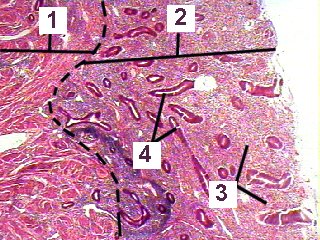

This is a higher magnificaiton of a section through the endometrium during the menstrual phase.

Fig 88-004 1. Myometrium

2. Endometrium

3. Ischaemic degenerating stroma

4. Degenerating glands